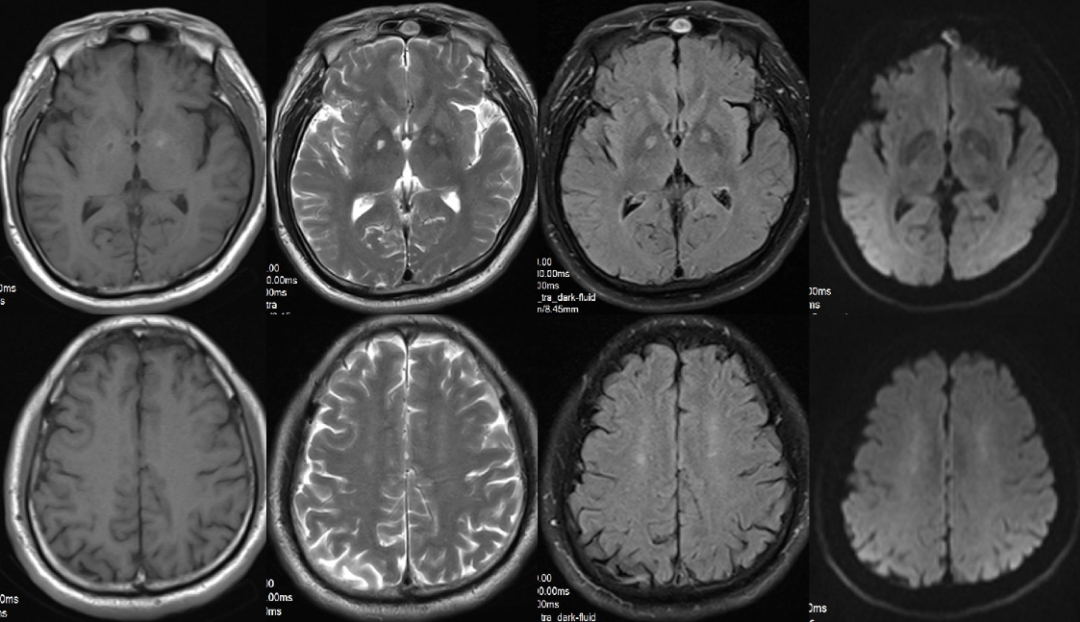

男,60 岁,一氧化碳中毒迟发性脑病,在经过急性期治疗后患者症状好转,进入 「 假愈期 」,实则疾病在进展,之后出现胡言乱语等,MR 表现双侧大脑半球皮层下深部白质对称性异常信号,T2WI、FLAIR 及 DWI 均呈高信号